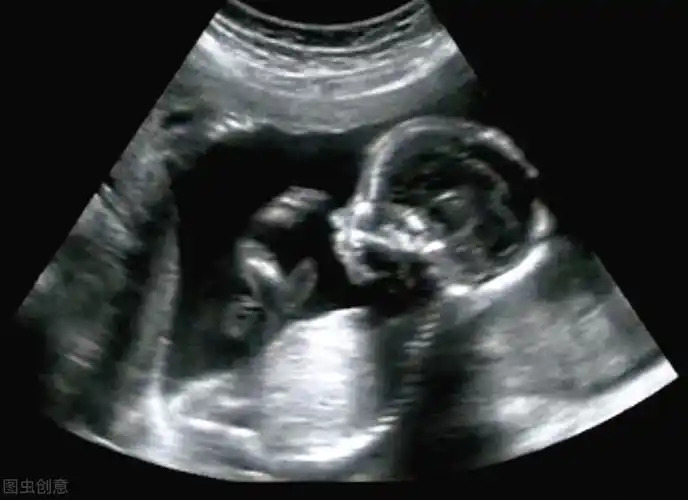

"看到娃四维照,我以为怀了外星人",孕期四维彩超为何丑出天际

胎儿四维照片丑哭,生出来会不会丑?知道原因后,孕妈可以放心了

"看到四维彩超的时候,我整个人都不好了,孩子的嘴巴怎么了,这是我孩子

四维彩超和宝宝的长相差别大吗?这些特征存在误差,丑俊难辨